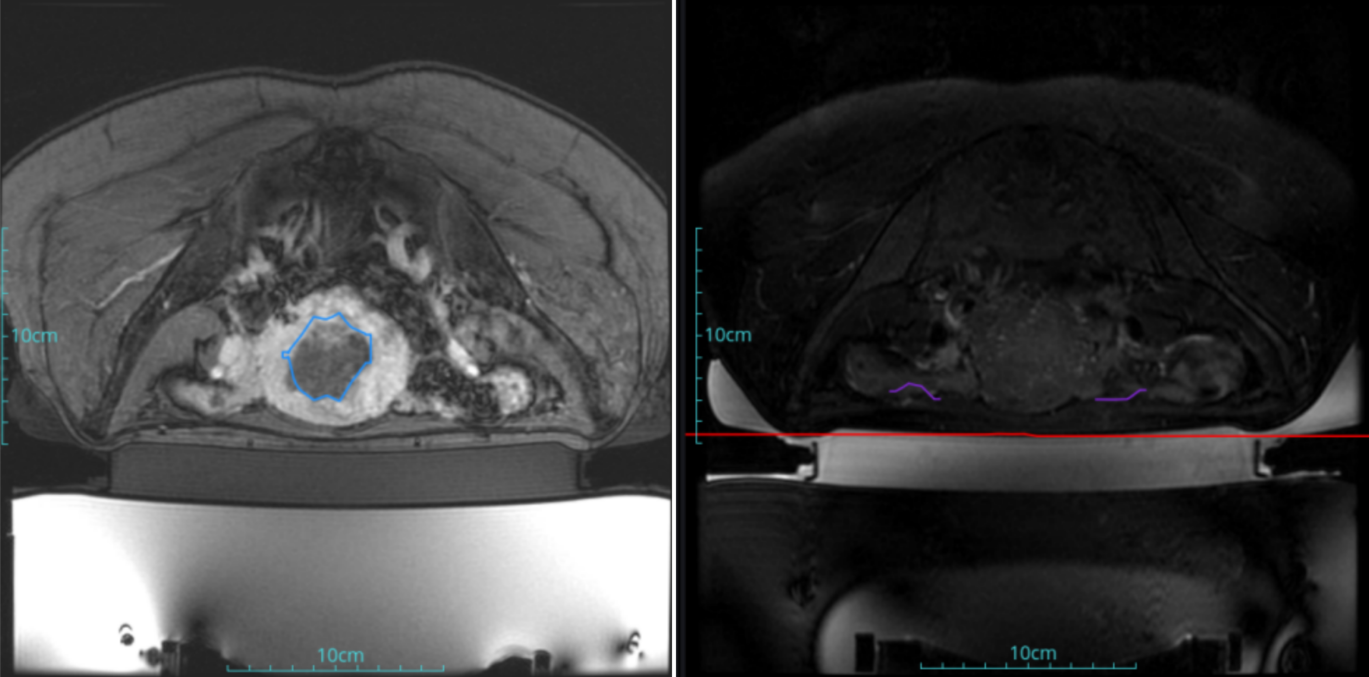

Postoperative evaluation: Postoperative enhanced imaging showed a good overlap between the ablation area (right) and the tumor area (left), the non-perfusion area was continuous and consistent.

Conclusion:It has a excellent ablation effect on this tumor, and the temperature rise curve during treatment is in line with expectations. The 240CEM area of each treated target is large, full and continuous.The ablation effect was very good,the NPV volume ratio was about 70%.